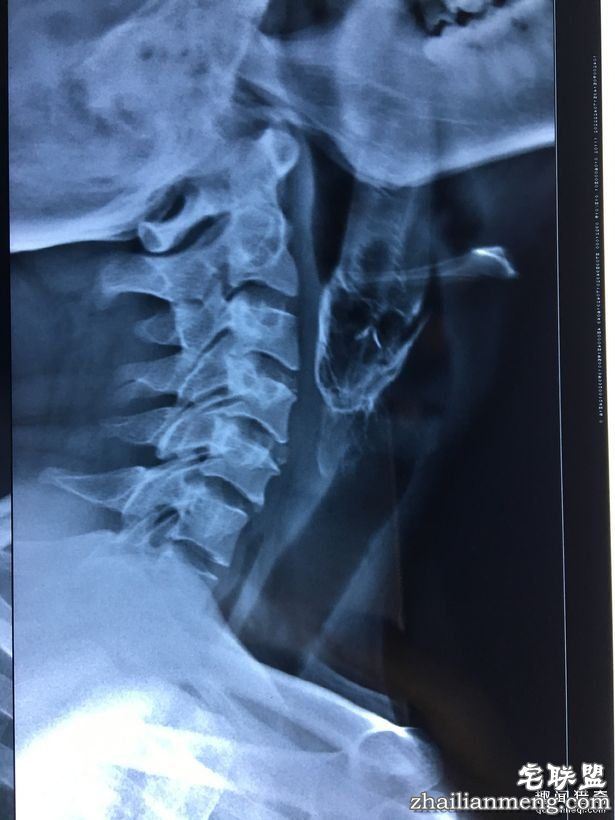

幸好,最后在医生帮忙下,终于把鱼取出来。负责的主治医生 Sanjeev Gupta说,他当下只看得见鱼的尾巴。「我们使用张口器,并用钳子抓住鱼,才慢慢成功拉出。」